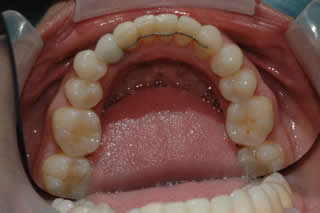

Orthodontic / Implant:

Lower left canine was extracted, thus teeth start drfting and tilting.

Space is re-created with orthodontics first, single implant was placed to replace the extracted canine.